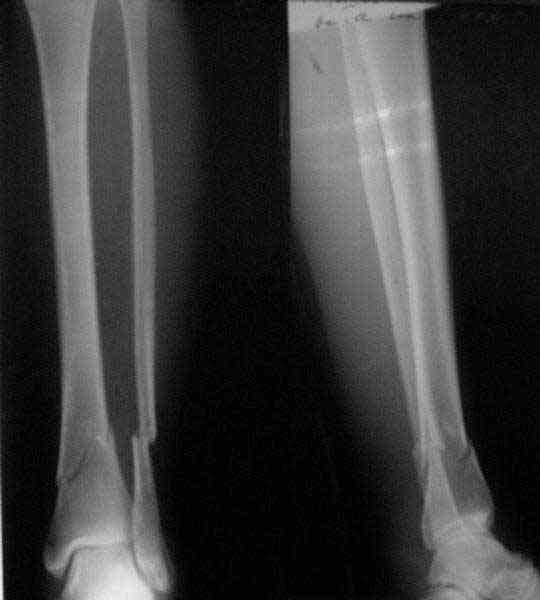

A typical case is attached, also an image with intra-op reduction obtained by a small wire distractor, in the moment of insertion a Poller wire in AP direction. Fixation by a SIGN nail. Despite the fibula was not fixed healing was obtained with the unchanged alignment.

Very interesting application, but is the final position in a little distal varus with some fibula

distraction? Would that have been eliminated by fibula plating?

TDVC> little distal varus with some fibula distraction?

At least both the ankle mortise and tibial alignment look acceptable, don't they?